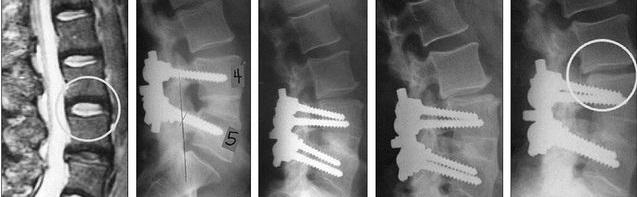

①初次手术由于腰背肌力量薄弱、髓核摘除不彻底等因素存在,术后患者直立位压力上升引起残留的间盘组织从纤维环破口再次突出;

③受固定的节段活动度受限制,相邻节段为了维持整个脊柱活动的平衡,代偿性地出现活动的增加、负荷增大,导致相邻节段退变加快;

④术中减压时对小关节内侧部分切除过多、间盘切除后椎间隙空虚、术后腰椎高能量活动等破坏腰椎稳定性,引起腰椎失稳;

⑤初次手术髓核被摘除后,相应节段椎间隙高度降低,前、后纵韧带松弛,导致椎管及神经根管容积减小;

⑥腰椎退行性变引起关节突增生、关节囊韧带增生及肥厚等均可导致椎管继发性狭窄;